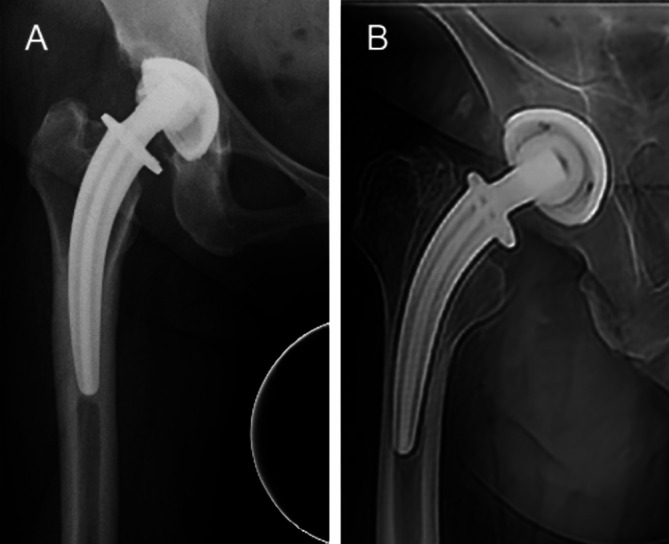

背景:全球全髋关节置换术(THA)的增加导致无水泥股骨干的广泛使用。colum Femoris Preserving (CFP)柄最初被设计为一种骨骺稳定假体,旨在保护近端骨并减少应力屏蔽。然而,长期观察显示意想不到的近端骨吸收和远端硬化,挑战了这种分类。本研究旨在重新评估CFP系统的固定模式和长期并发症,为临床决策提供依据。方法:2006年至2012年,纳入497例患者(705髋)。主要结果包括假体存活、假体周围骨重塑和临床结果,采用Harris髋关节评分(HHS)进行评估。Kaplan-Meier生存分析以假体松动和再手术为终点。影像学资料分析评估假体周围骨重塑。结果:共纳入497例患者(705髋),平均随访10.4年。CFP茎的长期生存率为95.32%,无菌性松动生存率为97.2%,再手术生存率为95.5%。并发症包括2.84%无菌性松动,0.99%感染,0.99%假体周围骨折,0.57%脱位,1.42%异位骨化。CFP假体没有无菌性松动的迹象,显示出远端稳定假体的影像学特征。结论:CFP假体的长期存活率为95.32%。影像学结果表明,CFP假体应被视为远端稳定假体,而不是传统意义上的骨骺稳定假体。

Results: A total of 497 patients (705 hips) with a mean follow-up of 10.4 years were included. The long-term survival rate of the CFP stem was 95.32%, with a 97.2% survival rate for aseptic loosening and 95.5% for reoperation. Complications included 2.84% aseptic loosening, 0.99% infection, 0.99% periprosthetic fractures, 0.57% dislocation, and 1.42% heterotopic ossification. The CFP stem, which has not shown signs of aseptic loosening, exhibits radiographic features characteristic of a distal-stabilized prosthesis.

Conclusion: The long-term survival rate of the CFP prosthesis was 95.32%. Radiographic findings indicate that the CFP prosthesis should be considered a distal-stabilized prosthesis rather than the traditionally regarded epiphyseal-stabilized prosthesis.